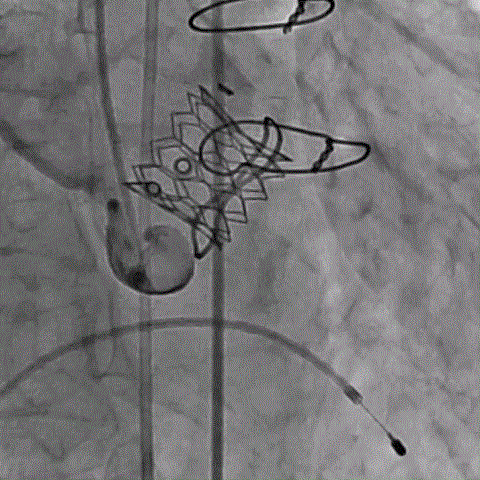

术前经详尽影像学重建和评估,该款人工生物瓣显影不理想,通过CT重建测量瓣环直径,评估冠脉梗阻风险。考虑到患者横位心,主动脉迂曲严重,最终选用经心尖入路,植入21# Renato球扩式瓣中瓣。手术顺利,瓣中瓣植入位置理想,功能表现出色,主动脉瓣峰值流速由术前3.4m/s下降至2.0m/s,平均跨瓣压差由术前32mmHg下降至8mmHg。经食道超声观察无瓣周漏及瓣中反流。

术前经详尽评估患者病情,通过CT重建测量瓣环直径、左室流出道面积。考虑到之前经房间隔入路外科换瓣,房间隔瘢痕严重,最终采用经心尖途径植入25# Renato球扩式瓣中瓣。手术顺利,瓣中瓣植入位置理想,功能表现出色,二尖瓣峰值流速由术前2m/s下降至1.4m/s,平均跨瓣压差由术前10mmHg下降至2mmHg,左室流出道压差正常,经食道超声观察无明显瓣中及瓣周返流。

术前经详尽影像学重建和评估,CT重建测量瓣环直径,评估冠脉梗阻风险及外周血管条件。最终采用经股动脉入路植入21# Renato球扩式瓣中瓣。手术顺利,瓣中瓣植入位置理想,功能表现出色,主动脉瓣峰值流速由术前4m/s下降至2m/s,平均跨瓣压差由术前40mmHg下降至6mmHg。经食道超声观察无瓣周漏及瓣中反流。